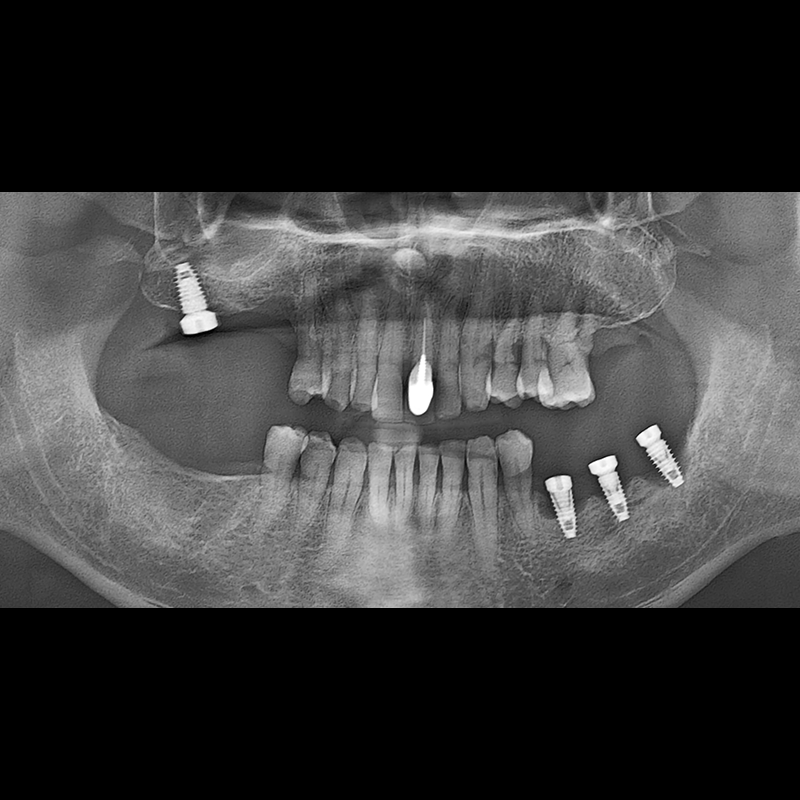

BEFORE AFTER

Implant before and after 2025.05.30

Implants were placed in the missing tooth and in the tooth position where it was difficult to save.